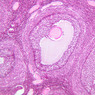

The resting or inactive mammary gland consists of predominantly dense connective tissue with small clusters of ducts and a few glandular elements (slide A-93 [2.5x-labeled, 10x, 20x, 40x] [1x, 2.5x, 10x, 20x]). It is difficult to differentiate between small ducts and alveoli as each is lined by simple low cuboidal cells. Lobes and lobules are not well defined. During puberty, predominantly under the influence of the ovarian hormone estrogen, the glandular or epithelial ducts proliferate and begin to differentiate into clusters of ductal and alveolar units termed terminal ductal lobule units (TDLUs). The non-pregnant gland will form multiple TDLUs that will not fully differentiate until pregnancy-induced growth. TDLUs are classified into Type I, Type II and Type III based on density of the ductules within each lobular unit. Type I and Type II lobules are typical of inactive glands that have not undergone a pregnancy cycle. Type III lobules are seen only in active glands or in inactive glands that have been through a pregnancy. Intralobular connective tissue is loose connective tissue that surrounds the alveoli and ducts within a lobule. The interlobular connective tissue is dense and contains considerable adipose tissue.

During pregnancy, predominantly under the influence of the ovarian hormone progesterone and the pituitary hormone prolactin, the glandular elements proliferate and differentiate to form milk-secreting units. In later stages of pregnancy, alveolar development becomes prominent and the amount of connective tissue and adipose tissue decreases. The secretory cells hypertrophy and accumulate secretory product.

The mammary gland in its active state is a compound tubuloalveolar gland (slide A-92 [10x, 20x, 40x-labeled] [2.5x, 10x, 20x, 40x]; A-94 [2.5x, 10x, 20x, 40x]). At this time, the gland is predominantly glandular tissue. Each alveolus is lined by a simple cuboidal epithelium. At the base of these cells, and within the alveolar basal lamina, are the stellate-shaped myoepithelial cells that are highly contractile and function to facilitate milk ejection.